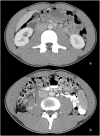

Retroperitoneal foreign bodies are rare indications for exploratory surgery. We present a case of a 19-year-old male with abdominal pain after a fall who was found to have a linear metallic object adjacent to the right ureter and inferior vena cava. Given the patient's pain and discomfort, he elected for robotic exploration of the retroperitoneum, which was carried out successfully with the Da Vinci Si® robot. This case demonstrates the feasibility of robotic retroperitoneal exploration and foreign body retrieval for a very small object.